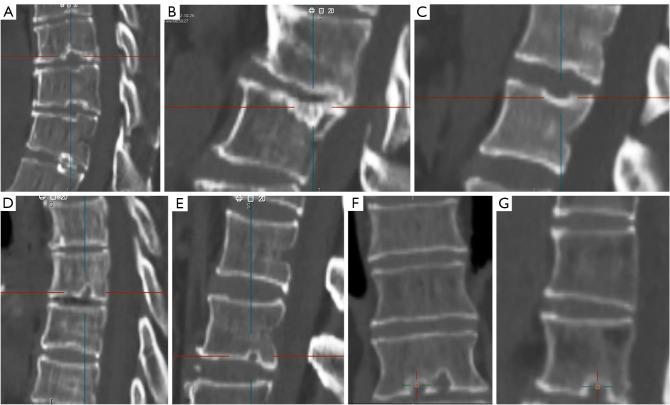

Cartilaginous endplate coverage of developmental Schmorl's node and the relevance of this in Schmorl's node etiology-based classification.

Quant Imaging Med Surg. 2024 Jun 1;14(6):4288-4303. doi: 10.21037/qims-24-335. Epub 2024 May 9.